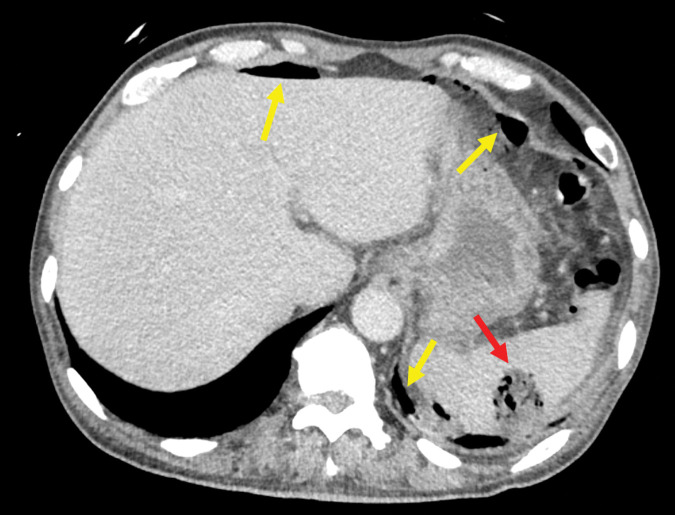

Case presentation: A 68-year-old man with uncontrolled diabetes presented with fever, chills, and abdominal pain. Initial evaluation at a previous hospital, including computed tomography (CT), suggested a lower gastrointestinal perforation, leading to his transfer to our facility. CT revealed a non-enhancing lesion with gas in the spleen and free intraperitoneal air; however, there was no clear evidence of gastrointestinal perforation. An emergency exploratory laparotomy was performed, which revealed purulent ascites and a ruptured splenic abscess without any gastrointestinal perforation. After thorough lavage to eliminate contamination, open abdominal management was initiated owing to a need for catecholamine support and an inability to completely rule out the possibility of gastrointestinal perforation. A second-look laparotomy confirmed that there was no further contamination or gastrointestinal tract perforation. Blood and abscess cultures revealed Escherichia coli, leading us to initiate targeted antibiotic therapy. The patient recovered successfully and was discharged on postoperative day 40 without any recurrence. Ruptured splenic abscess with pneumoperitoneum is rare and poses significant diagnostic challenges, particularly in patients with diabetes, owing to its clinical similarity to gastrointestinal perforation. This study highlights the utility of exploratory laparotomy and staged open abdominal management when gastrointestinal perforation cannot be ruled out.